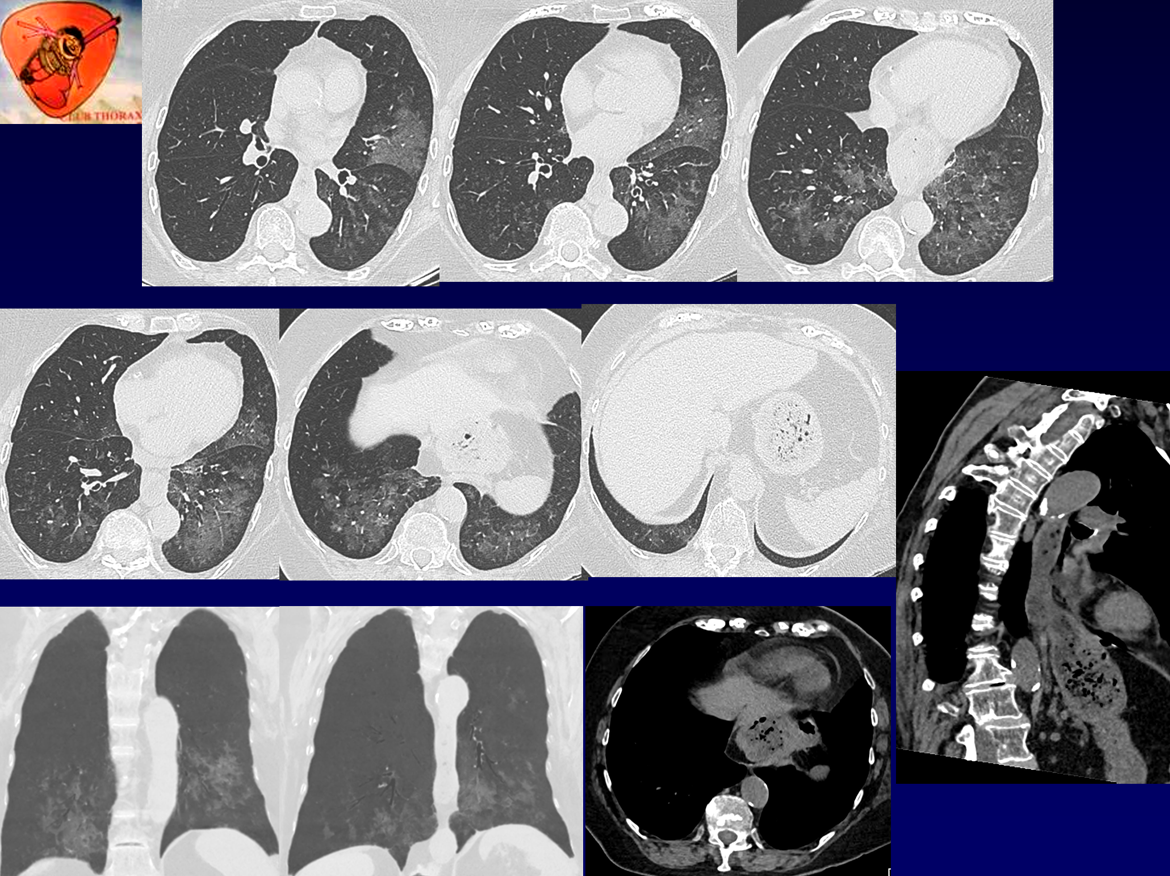

QUIZ N° 011

F, 76 ans, toux chronique.

ATCD: Volvulus gastrique opéré en 2017

RGO: Inexium - Gaviscon

EFR: TVO, VEMS à – 22%, Tiffeneau 72%, CPT et DLCO Nles

QUEL EST VOTRE DIAGNOSTIC ?

A – PINS

B – PHS pneumopathie d’hypersensibilté

C – PO pneumopathie organisée

D – Pneumopathie lipidique & RGO

E – Sarcoïdose & RGO